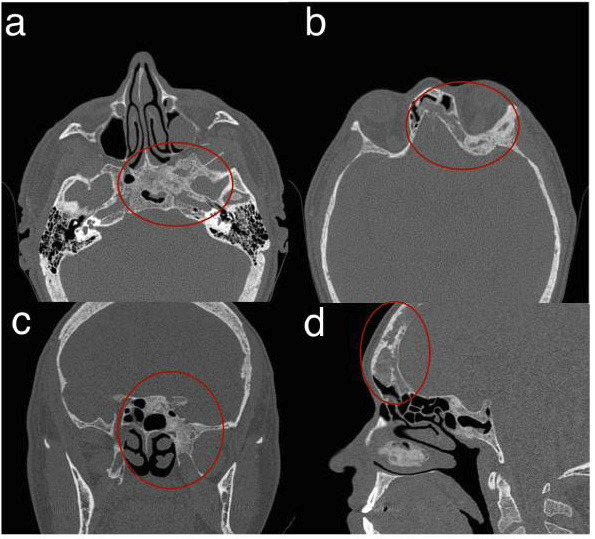

This case report describes a rare, asymptomatic brown tumor in a patient with end-stage renal disease. The lesion was incidentally detected during a computed tomography (CT) scan of the paranasal sinuses, performed upon a dentist's recommendation to investigate maxillary sinusitis. CT imaging revealed an expansive osteolytic lesion with irregular margins and a ground-glass appearance involving the left side of the sphenoid and frontal sinuses. Subsequent magnetic resonance imaging (MRI) with multiplanar T1 and T2-weighted sequences without contrast demonstrated a solid tissue-like expansive lesion affecting the left frontal and sphenoid bones, mildly compressing adjacent cerebral parenchyma. Despite these findings, the patient remained asymptomatic. Conservative management, including pharmacological therapy with calcimimetics to control parathyroid hormone levels, was initiated. A follow-up MRI after five years showed lesion stability without significant changes. The patient later underwent a renal transplant, which effectively stabilized the bone disease and improved his quality of life. This case underscores the pivotal role of computed tomography (CT) in detecting incidental systemic skeletal changes and the indispensable importance of interdisciplinary collaboration in managing complex conditions in systemically compromised patients, where each professional's expertise is crucial for the patient's well-being. Key words:Sinusitis, Brown Tumor, Hyperparathyroidism, Multidetector Computed Tomography, Magnetic Resonance Imaging, Multidisciplinary Care Teams.